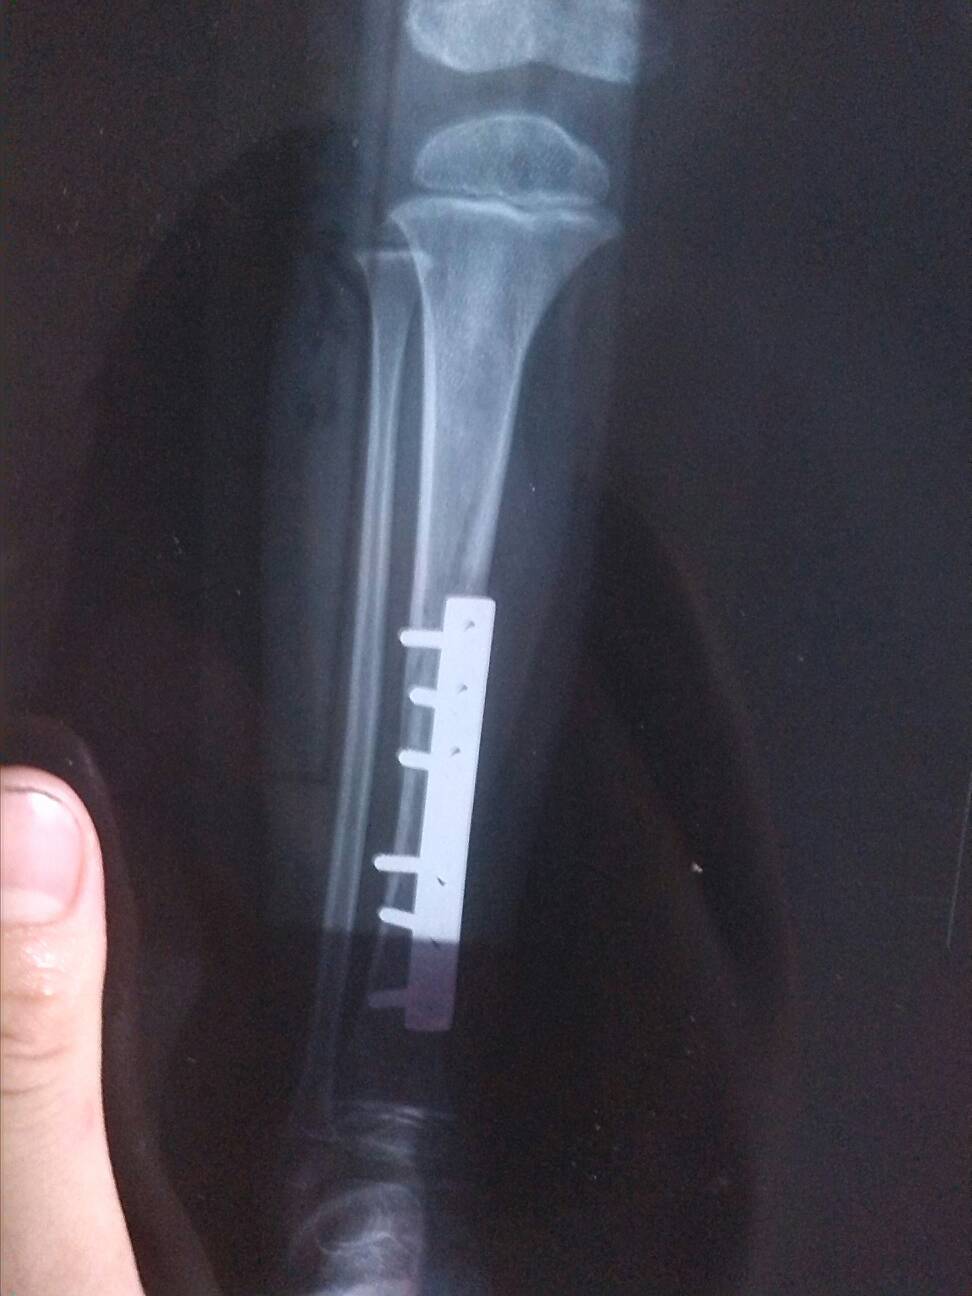

三岁宝宝骨折手术后,一个多月拍片对位不太好,但愈合良好 请专家看看要紧吗会有后遗症吗(附图) 点击展开 匿名用户 2014-08-05 15:32 为您推荐: 其他回答 你好,这个是不用担心的呢,自己这个时候还是要多注意好好的休息一下的啊,这样是会更好的呢 可靠的悠闲80 2014-08-06 09:28 相关问题 问一下医生,为什么我爱人小手指骨折了,在医院做完手术,用钢针固定,现在五个月了,拍片看还是没有愈合 骨股颈骨折后,已三个月 复查拍片,结论有对位、对线… 小孩右肱骨骨折,石膏固定30天了,拍片检查骨折要愈合到什么程度才可以拆石膏